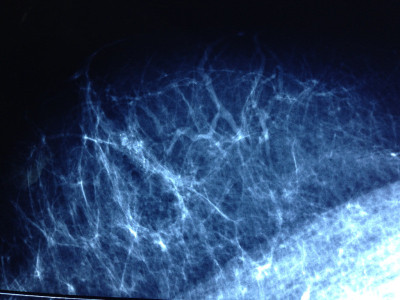

Mamografía de rutina con calcificaciones sospechosas.